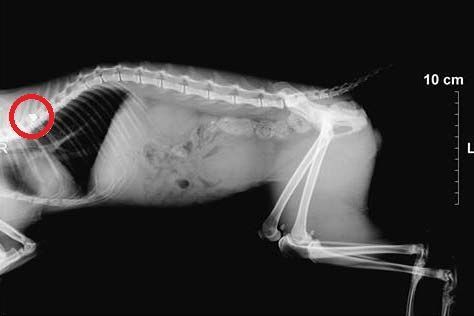

MelissiaPyrovolimeniAktinografiaΗ ακτινογραφία έδειξε σε ποιο σημείο έχει σφηνώσει το σφαιρίδιο του αεροβόλου.

Η ακτινογραφία απέδειξε ότι το σφαιρίδιο του αεροβόλου σφηνώθηκε στην σπονδυλική στήλη του ζώου με αποτέλεσμα τα πίσω άκρα του γάτου να παραλύσουν και φυσικά να χρειάζεται βοήθεια και για την ούρηση καθώς δεν μπορεί να ελέγξει ούτε αυτή τη λειτουργία του σώματος του.

AktinografiaMelissiaPyrovolimeno (1)Μη αναστρέψιμη η κατάσταση της υγείας του.